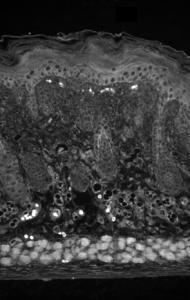

Supportive validation

- Submitted by

- OriGene (provider)

- Main image

- Experimental details

- IHC analysis of Kir2.2 in mouse backskin sections.

- Validation comment

- IHC